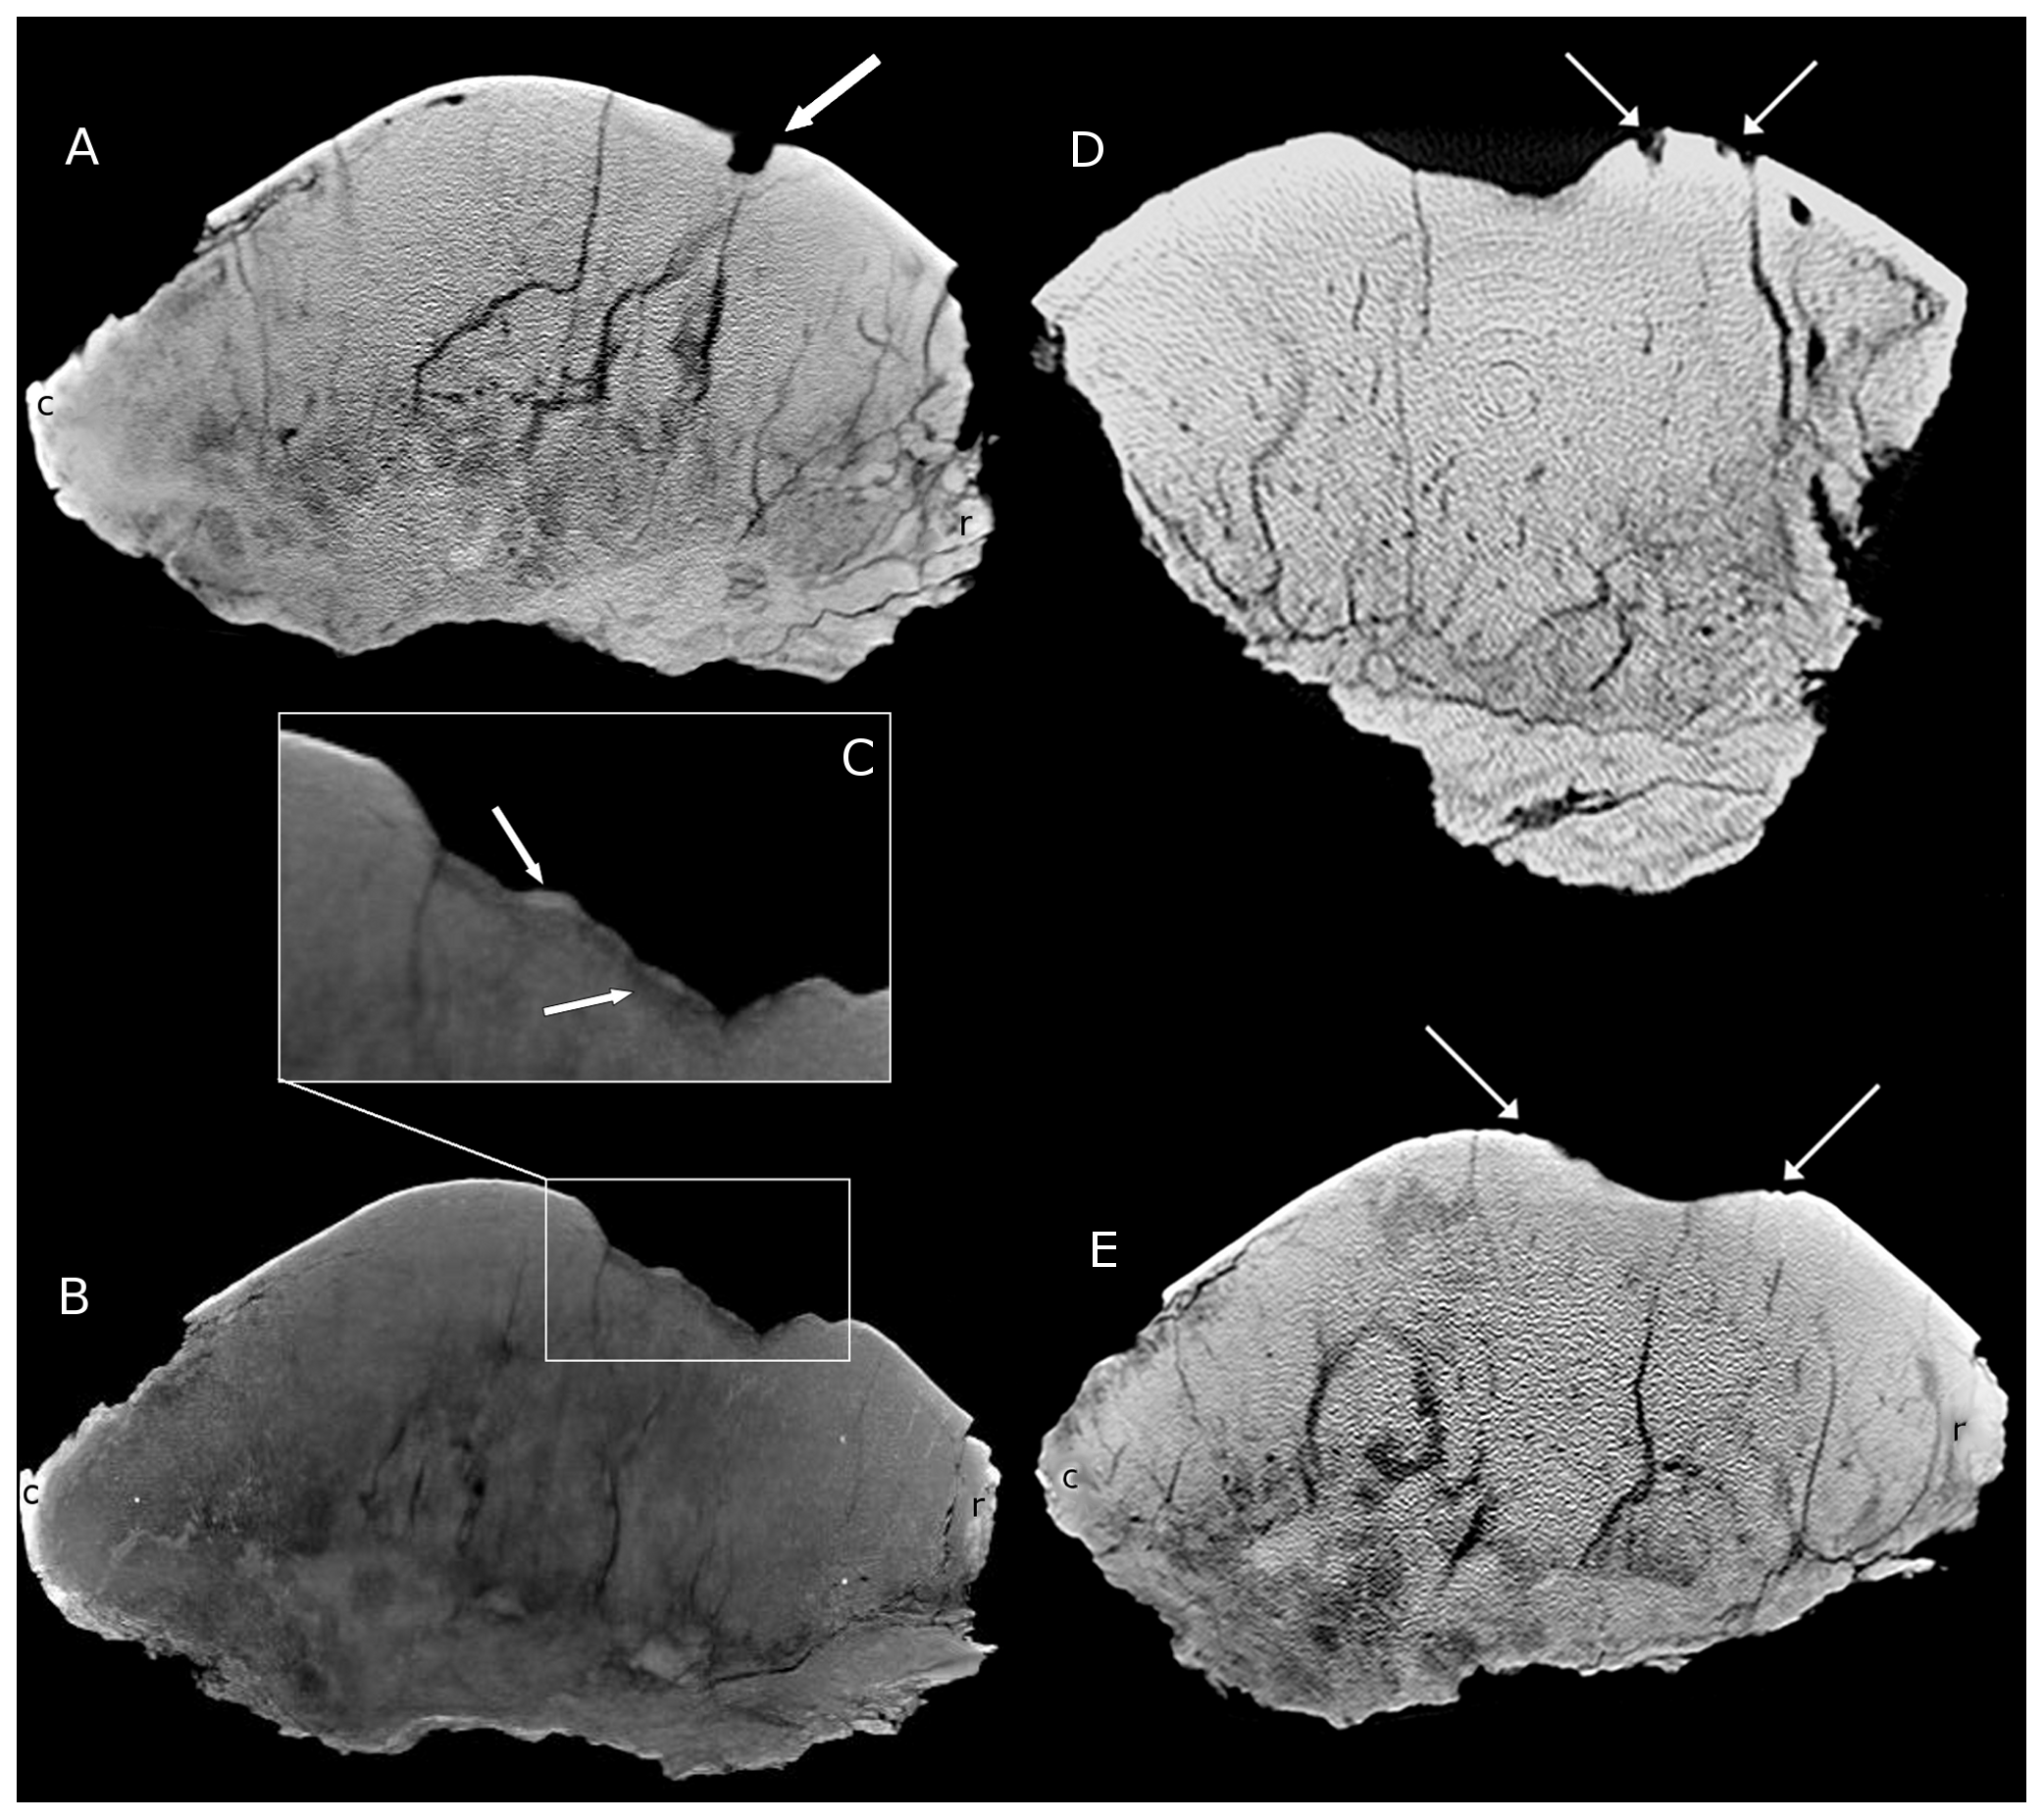

Cranial Pathologies in a Specimen of Pachycephalosaurus

Peterson, J.E. & Vittore, C.P. · PLOS ONE

Primeiro estudo sistemático de patologia craniana em um espécime identificado como Pachycephalosaurus wyomingensis (espécime BMR P2001.4.1 do Museu de Paleontologia Burpee). Peterson e Vittore descrevem duas grandes depressões ovaladas na superfície dorsal da cúpula, acompanhadas de inúmeras cavidades circulares. Tomografia computadorizada revela que as lesões penetram profundamente o osso. A análise comparativa com aves modernas com traumatismo craniano por infecção indica que as estruturas são lesões patológicas resultantes de ferimento traumático seguido de osteomielite secundária. O estudo fornece evidência física direta de que a cúpula de Pachycephalosaurus sofria danos compatíveis com combate agonístico, estabelecendo o alicerce para o trabalho mais amplo de Peterson et al. (2013).

Distributions of Cranial Pathologies Provide Evidence for Head-Butting in Dome-Headed Dinosaurs (Pachycephalosauridae)

Peterson, J.E., Dischler, C. & Longrich, N.R. · PLOS ONE

Estudo definitivo sobre o comportamento de choque de cabeças em pachicefalossaurídeos, baseado na análise sistemática de 109 cúpulas cranianas de espécimes adultos. Peterson, Dischler e Longrich encontram que 22% dos espécimes adultos com cúpula desenvolvida apresentam lesões patológicas concentradas no ápice da cúpula, compatíveis com osteomielite crônica resultante de traumatismo repetido e infecção secundária. Formas de cabeça plana, interpretadas como juvenis ou fêmeas, não apresentam patologias. O padrão de distribuição das lesões, a composição de osso fibrolamelado com fibroblastos capazes de remodelação rápida e a comparação com bovídeos modernos que se combatem sustentam o comportamento de choque de cabeças e/ou flancos como habitual nos pachicefalossaurídeos adultos de cúpula desenvolvida.